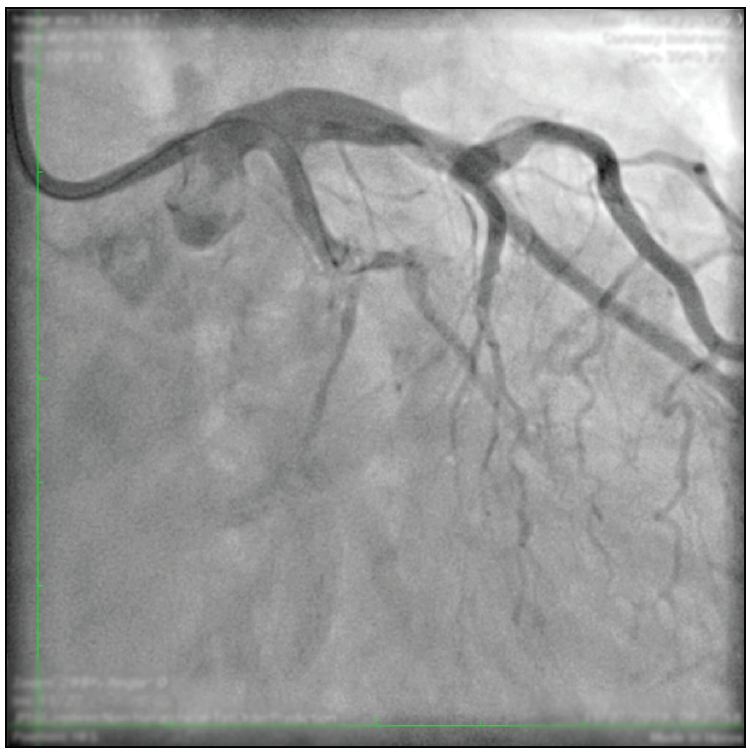

A 62-year-old man with non–insulin-dependent diabetes and no cardiac history was diagnosed with angina pectoris Canadian Cardiovascular Society grade II by means of a positive stress echocardiogram at the inferior and posterior left ventricular wall with normal systolic function. Diagnostic angiography revealed two-vessel disease: a severely calcified subocclusive lesion in the left circumflex artery (LCX) at the first obtuse marginal (OM1) branch bifurcation as the main culprit vessel (Figure 1) and a long chronic total occlusion (CTO) at the mid-right coronary artery (RCA) with excellent retrograde filling flow from the left anterior descending (LAD) artery.